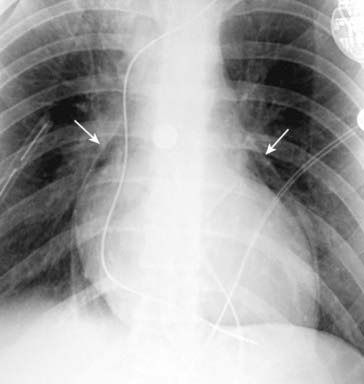

image

Figure 8-3 Pneumothorax with pleural adhesions.

Lung markings may be visible on a conventional radiograph of the chest, distal to the visceral pleural line if pleural adhesions are present. In (A), a pneumothorax (solid white arrows) is prevented from collapsing the lung by pleural adhesions (solid black arrows). On a CT scan (B), the pleural adhesions (solid black arrows) are seen tethering the lung (solid white arrows) to the parietal pleura. Adhesions most frequently result from prior infection or blood in the pleural space.

On conventional radiographs, it may be possible to visualize lung markings in front or in back of the pneumothorax and to overlook the presence of a pneumothorax because lung markings appear to extend to the chest wall.

Absence of lung markings alone is not sufficient for the diagnosis of pneumothorax nor is the presence of lung markings distal to the visceral pleural line sufficient to eliminate the possibility of a pneumothorax.